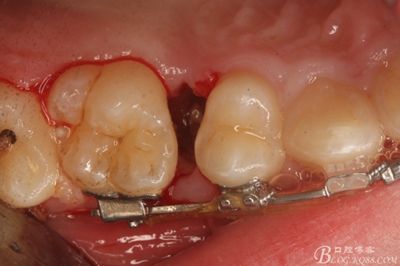

圖11.仔細考慮之后,在14頰側做垂直切口,切口長度僅達膜齦聯(lián)合處,做小切口。

圖12. 做垂直切口+齦溝內(nèi)切口,形成角形瓣,暴露出15根面。

圖13. 用小球鉆去除約1mm牙槽骨,暴露15牙根面約5mm。